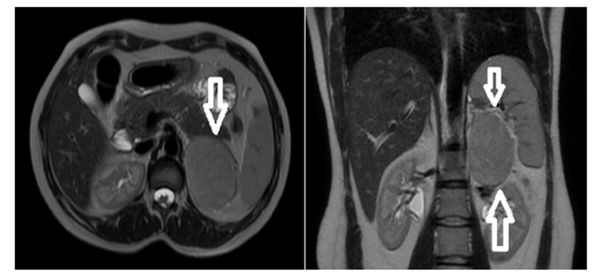

Cortisol evaluation revealed hypercortisolism with a cortisol level of 21.3μg/dL, suppressed ACTH of <1.5ng/L (normal range: 7.2-63.3ng/L), and elevated 24-hour urinary free cortisol of 562μg/24h (normal: <130μg/24h). The 1-mg dexamethasone suppression test showed failure to suppress with a cortisol level of 20.8μg/dL. Plasma metanephrine and normetanephrine levels were normal, excluding pheochromocytoma. Aldosterone and plasma renin activity were within normal limits. Given the biochemical evidence of combined hypercortisolism and hyperandrogenism, Magnetic Resonance Imaging (MRI) of the abdomen was performed. This revealed a 76×57mm well-circumscribed mass in the left adrenal gland that was isointense on both T1-weighted and T2-weighted sequences, demonstrated diffusion restriction, and showed progressive enhancement after intravenous contrast administration. The splenic vein was in close proximity to the anterior aspect of the mass, and the ipsilateral kidney showed a compression effect. Small retroperitoneal lymph nodes were noted. The imaging characteristics, combined with the large size and hormonal profile, raised concern for adrenocortical carcinoma. 18F-fluorodeoxyglucose positron emission tomography/computed tomography (18F-FDG PET/CT) was performed to evaluate for metastatic disease. The left adrenal mass demonstrated moderate FDG uptake with a maximum Standardized Uptake Value (SUVmax) of 7.2. No evidence of metastatic disease was identified (Figure 1).

Figure 1:Dynamic contrast-enhanced MR imaging shows a mass lesion that is isointense on T2W and T1W series with regular borders and limited diffusion, and that enhances progressively after IVCM.